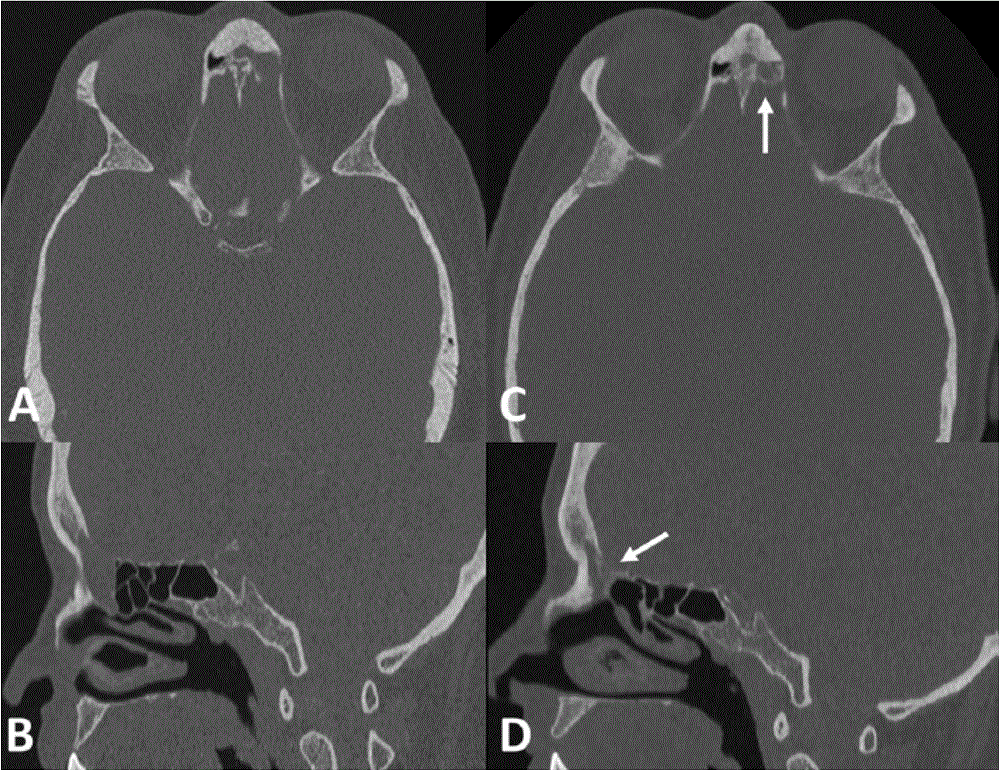

Méningocèle du sinus frontal gauche. A et B avant traitement; C et D après traitement endoscopique (flèche blanche montrant un comblement fibreux)

Les brèches de liquide céphalorachidien et méningocèles

Qu’elles soient spontanées ou post-traumatiques, les brèches et les méningocèles (hernie cérébrale à travers une paroi du sinus frontal) nécessitent un traitement chirurgical pour éviter le risque de méningite ou d’abcès cérébral.